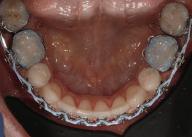

20 Dental Tribune Bulgarian Edition / октомври 2022 г. П ациентите със завършен растеж и скелетни проблеми обикновено представляват предизвикателство за ортодонт ската практика. Необходимостта от изваждане на зъби в комбинация с особеностите на възрастовата ортодонтия изисква особено внима ние. Фокусът върху критично важното значение на позицията на долните резци във връзка с дългосроч ната стабилност и постигането на оптимални оклузални взаимоотношения при затварянето на екстракционните пространства лесно може да излезе извън контрол. Когато към тези чисто кли нични проблеми се добави и стресът от натоваре ната практика, предизвикателството става още по-голямо. Всички тези фактори налагат използ ването на доказан подход с ясни и последовател ни стъпки, в което се разкрива силата на дисциплината „Алекзандър“ – предвидим протокол през целия процес на елиминиране на ротациите, ниве лиране на дъгите, затваряне на екстракционните пространства и финализиране на случая. Именно такъв е и случаят, който презентираме –екстракционен, скелетен клас 3 при възрастен па циент, лекуван по системата „Алекзандър“. ПРЕДВИДИМИ РЕЗУЛТАТИ ПРИ ПАЦИЕНТИ СЪС ЗАВЪРШЕН РАСТЕЖ И СКЕЛЕТЕН КЛАС 3, ИЗПОЛЗВАЙКИ ЕКСТРАКЦИОННО ЛЕЧЕНИЕ ПО ДИСЦИПЛИНАТА „АЛЕКЗАНДЪР“ Д-р Радой Димитров, България Преди започване на лечение клиничен случай | ортодонтия Фиг. 1а–1e Преди започване на лечение. Пациентът пристига в практиката с основното оплакване от невъзмож ност за нормално дъвчене. Снета е цялата необходима диагностична ин формация. Фиг. 1f–1h Снимки в профил и анфас. Фиг. 1i–1k Панорамна снимка, телерентгенография и анализ на телерент генография. Фиг. 1а Фиг. 1d Фиг. 1f Фиг. 1g Фиг. 1h Фиг. 1e Фиг. 1b Фиг. 1c Фиг. 1i Фиг. 1j Фиг. 1k

closed.

21Dental Tribune Bulgarian Edition / октомври 2022 г. ДИАГНОСТИЧНИ РЕЗУЛТАТИ: 1. Възраст на пациента: 21 години 2. Скелетен клас III (ANB 0) 3. Зъбен клас 3 4. Ръбцова захапка във фронта, кръстосана в дисталните участъци 5. Тясна горна челюст 6. Overjet – 0 мм, Overbite – 0 мм 7. Несъответствие на горната с долната средна линия 8. Единични контакти в ЦО 9. Хиподивергентен тип на растеж SN/MP – 33.5 10. Неравен гингивален контур 11. Неравна линия на усмивката 12. Тенденция за рецесии в долен фронт ПРЕПОРЪЧИТЕЛНО ЛЕЧЕНИЕ: Пълно ортодонтско лечение с метални брекети „Алекзандър“ Корекция на клас 3 захапката в областта на кучешките зъби с екстракция на първите пре молари в долна челюст Корекция на кръстосаната захапка в дистални участъци Коригиране на ръбцовата захапка във фронта Подобряване на ОJ и OB на пациента Стрипинг в долен фронт Подреждане на зъбите в горната и долната челюст Професионално хигиенизиране и профилактични дентални прегледи са препоръчителни на всеки 6 месеца. 1-ви месец След 1 месец са залепени брекети в горната челюст – поставена е еластична дъга. 016 NiTi. В долната челюст са елиминирани ротациите, поставена е стоманена дъга. 016SS, закалена с ток, и еластична верижка за затваряне на пространствата. 3-ти месец В долната челюст е поставена трета дъга – 17 x 25 NiTi с къси лигатури и верижка

В горната челюст се затварят пространствата с дъга .016SS и верижка. 5-и месец На 5-ия месец след залепяне на брекетите в долната челюст е поставена стоманена дъга 16 x 22 SS с четвъртито сечение, омега луп и тай бек. В горната челюст е поставена дъга 17 x 25 NiTi. Поради липсата на стабилни оклузални контакти са поставени лингвални верижки в областта на моларите, за да се предотврати нежелана ротация на 7-ите зъби. 6-и месец На 6-ия месец от началото на лечението са екстрахирани долните първи премолари, поставена е дъга 16 x 22 SS със затваряща чупка teardrop. Чупката се активира всеки месец по 1 мм с чинч-бек. клиничен случай | ортодонтия СТЪПКИ НА ЛЕЧЕНИЕТО Начало на лечението Лечението започва с поставяне на апарат за бърза експанзия в горната челюст. През първия месец от лечението са направени 24 оборота на апарата за експанзия. Залепени са брекети в долната челюст, поставена е дъга 17x25 CuNiTi, като са предпи сани клас 3 ластици (1/4”,4 1/2 oz) по време на сън, за да се осигури контрол върху торка на долните резци. Фиг. 2а Фиг. 3a Фиг. 4a Фиг. 3b Фиг. 4b Фиг. 3c Фиг. 4c Фиг. 3d Фиг. 4d Фиг. 3e Фиг. 4e Фиг. 5a Фиг. 5b Фиг. 5c Фиг. 5d Фиг. 5e Фиг. 6a Фиг. 6b Фиг. 6c Фиг. 6d Фиг. 6e Фиг. 7a Фиг. 7b Фиг. 7c Фиг. 7d Фиг. 7e Фиг. 2b Фиг. 2c Фиг. 2d